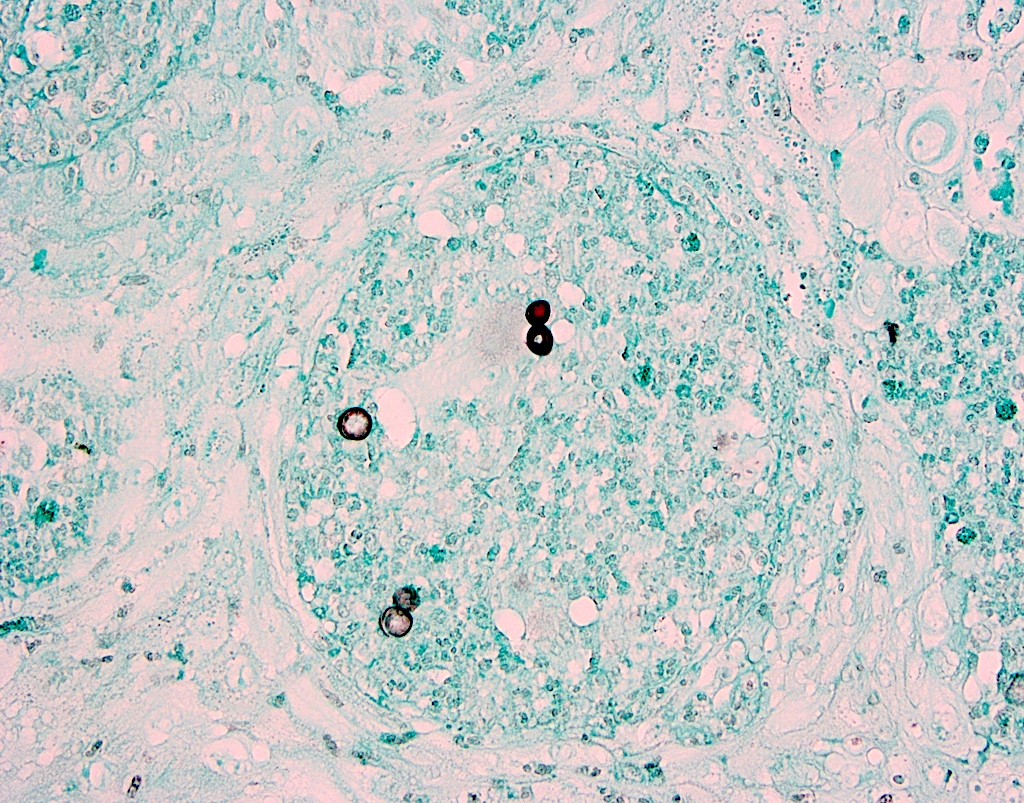

PEH in blastomycosis PEH in blastomycosis

PEH in blastomycosis

Pseudoepitheliomatous Hyperplasia in Blastomycosis Infection of the Skin

PEH in blastomycosis infection of the skin

Practice question #3

The above biopsy was taken from a patient with a large, indurated ulceration on the tongue. What is the diagnosis?

1. Blastomycosis with pseudoepitheliomatous hyperplasia

2. Granulomatosis with polyangiitis

3. Pyogenic granuloma

4. Squamous cell carcinoma

Practice answer #3

A. Blastomycosis with pseudoepitheliomatous hyperplasia. Blastomycosis is one of the conditions that characteristically shows pseudoepitheliomatous hyperplasia (PEH) in which the epithelium is thickened and forms elongated and anastomosing rete ridges. Answer D is incorrect because although blastomycosis has often been misdiagnosed as squamous cell carcinoma (SCC) due to this prominent PEH, neutrophilic abscesses throughout the epithelium should prompt the pathologist into getting infectious stains, such as the GMS shown above. The GMS stain highlights the thick walled blastomycosis organisms, which show broad based budding. SCC is a common pitfall in the diagnosis of blastomycosis but is incorrect because fungal stains are negative for deep organisms in SCC. Answer B is incorrect because granulomatosis with polyangiitis (GPA) also demonstrates dense inflammation and PEH; however, GPA has evidence of vasculitis and a lack of deep fungal organisms. Answer C is incorrect because pyogenic granulomas can also show dense inflammation and some degree of PEH; however, the epithelium is often not this prolific and microorganisms would not be present on GMS staining.